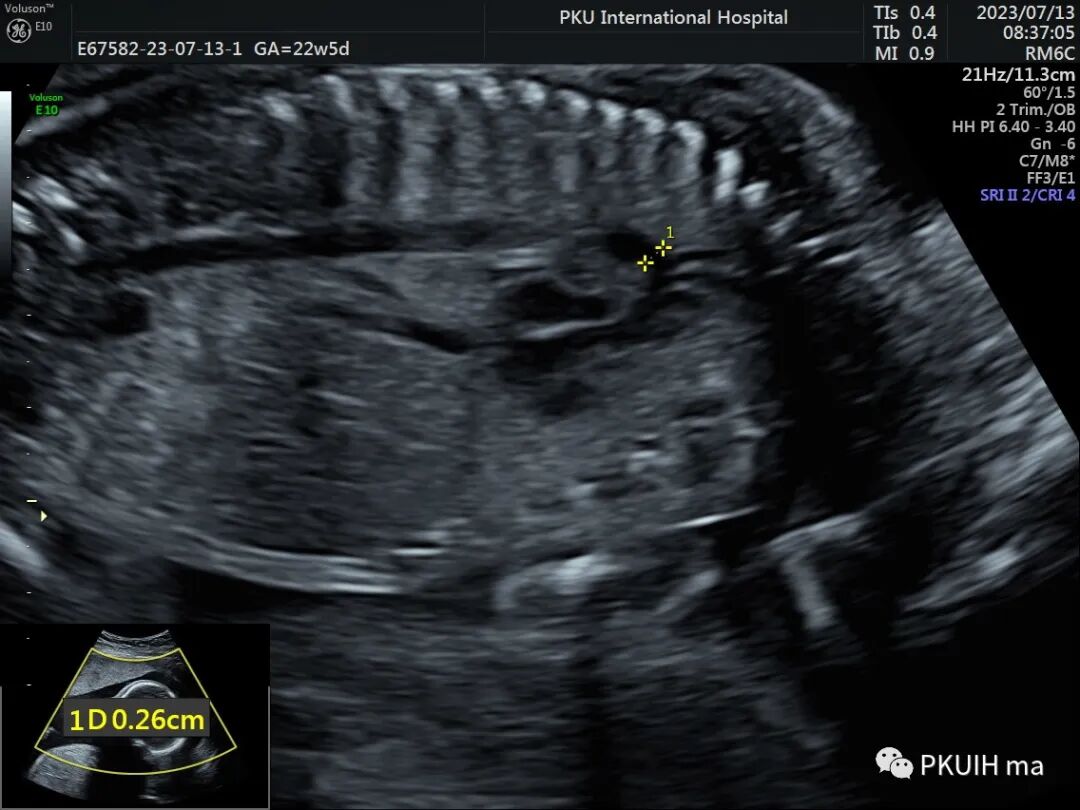

首先我们要通过四腔心切面观察左右心比例。孤立性CoA四腔心切面显示左右心比例失调,左心小右心大(如下图)。当右室与左室横径比值>1.6时提示可能存在CoA。中孕期敏感度较高,晚孕期可出现假阳性。可以通过测量左室内径、二尖瓣环内径及主动脉瓣环内径计算Z值,内径小Z值<–2提示CoA发生风险增高。